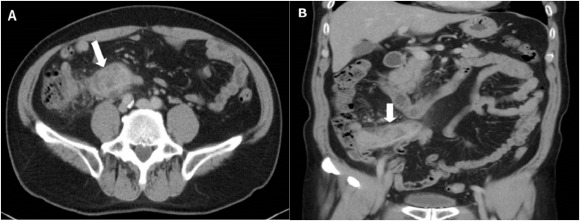

A 67-year-old man came to the outpatient department with intermittent right lower abdominal pain ongoing for 1 month. He denied any systemic disease and had no fever, chills, hematochezia, chronic diarrhea, nor body weight loss. Physical examination revealed right lower quadrant tenderness without rebound pain and muscle guarding. Positive psoas sign was noted. Blood tests were unremarkable except mild elevated C-reactive protein (4.9 mg/dL). Abdominal computed tomography (CT) demonstrated marked appendiceal wall swelling and intraluminal filling defect of contrast medium over the appendix (Figure 1). The colonoscopy revealed a protruding mass with edematous mucosa at cecum (Figure 2). Biopsy obtained at colonoscopy revealed inflammation of appendix mucosa. Due to the cancer could not be ruled out, a surgery with right hemicolectomy was performed and which showed a 7-cm length appendiceal tumor (Figure 3). Hematoxylin and eosin staining showed irregular glands with stromal invasion to muscularis propria, intraluminal mucin extravasation, and abscess formation were also seen (Figure 4A). Glandular arrangement lining by pseudostratified columnar cells with enlarged vesicular nuclei was noted under high magnification (Figure 4B). On the basis of these findings, he was diagnosed as colonic type adenocarcinoma of the appendix, T2N0M0, Stage I. After right hemicolectomy, he remains asymptomatic to date.

Figure 2. A protruding mass with edematous mucosa noted at cecum. |